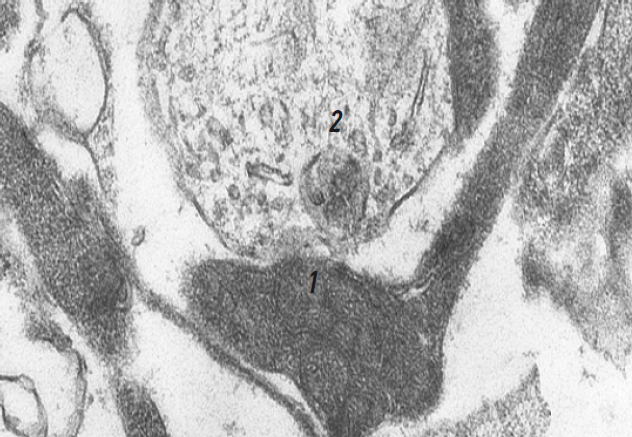

In the control group, the lumbar segment of the spinal cord predominantly contained hyperchromic neurons, characterized by densely structured nuclei and cytoplasm. These neurons exhibited a greater number of mitochondria; however, many exhibited indistinct structural features, suggesting low activity (Fig. 1). The surrounding myelinated and unmyelinated fibers were markedly altered.

Fig. 1. Hyperchromic neuron rat spinal cord without treatment: 1 — nucleus; 2 — mitochondria (arrow), ×8,300.

Рис. 1. Гиперхромный нейрон спинного мозга крысы без лечения: 1 — ядро; 2 — митохондрии (стрелка), ×8 300.